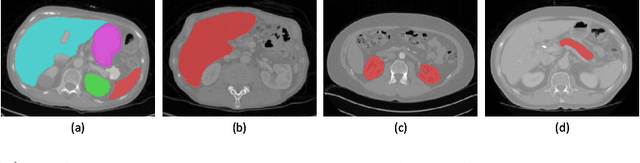

Multi-organ segmentation has extensive applications in many clinical applications. To segment multiple organs of interest, it is generally quite difficult to collect full annotations of all the organs on the same images, as some medical centers might only annotate a portion of the organs due to their own clinical practice. In most scenarios, one might obtain annotations of a single or a few organs from one training set, and obtain annotations of the the other organs from another set of training images. Existing approaches mostly train and deploy a single model for each subset of organs, which are memory intensive and also time inefficient. In this paper, we propose to co-train weight-averaged models for learning a unified multi-organ segmentation network from few-organ datasets. We collaboratively train two networks and let the coupled networks teach each other on un-annotated organs. To alleviate the noisy teaching supervisions between the networks, the weighted-averaged models are adopted to produce more reliable soft labels. In addition, a novel region mask is utilized to selectively apply the consistent constraint on the un-annotated organ regions that require collaborative teaching, which further boosts the performance. Extensive experiments on three public available single-organ datasets LiTS, KiTS, Pancreas and manually-constructed single-organ datasets from MOBA show that our method can better utilize the few-organ datasets and achieves superior performance with less inference computational cost.